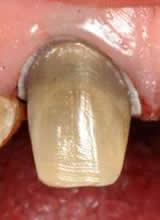

On your initial appointment the dentist will locate the offending tooth and take an x-ray in order to show the roots of the tooth, to see how far the decay has travelled and if there is an abscess present. A course of antibiotics may be given to clear the abscess before the treatment is started as the abscess will reoccur if the treatment is NOT carried out.

• Your dentist has to gain access to the pulp chambers, this is done by drilling a hole in the top of your tooth.

• Once access has been gained to the pulp chambers the dead pulp is removed from the root canals using very small files and a hydrochloric wash. An additional x-ray will be taken at this point.

• Your dentist may advise you to have a crown placed on the tooth to strengthen it.